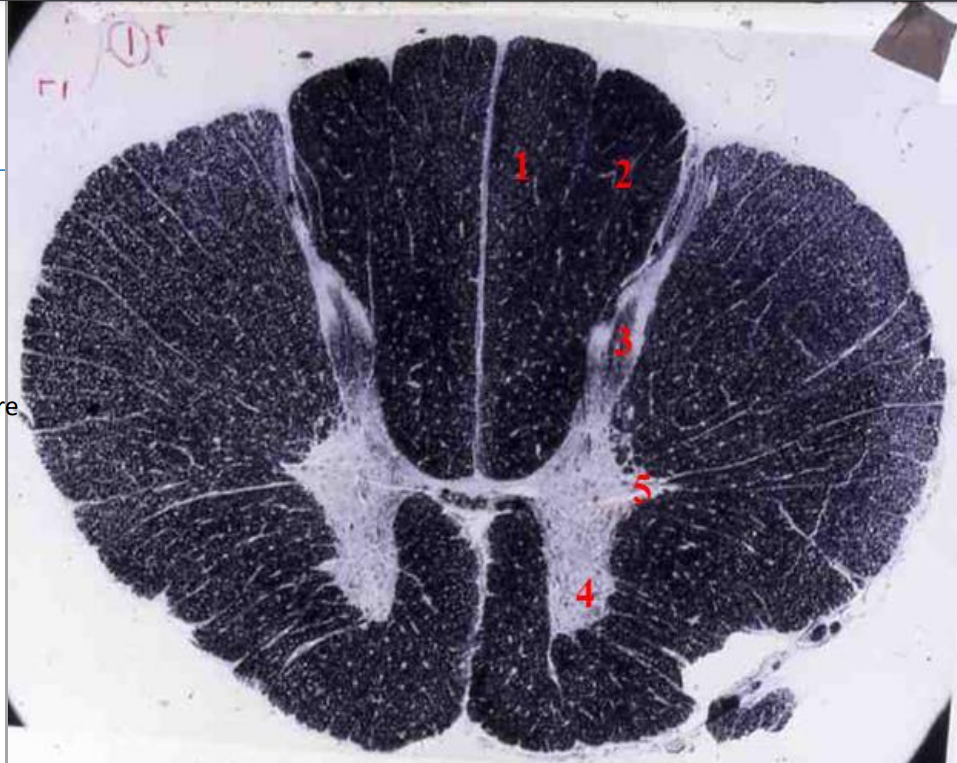

thoracic cord

- Fibre tracts are larger

- Grey matter is scanty as no limb plexuses

1

A

fasciculus gracilis

How well did you know this?

fasciculus cuneatus

- dark tracts

- heavilty myelinated

- for fast conduction

posterior horn

anterior horn

lateral horn

- sympathetic neurons